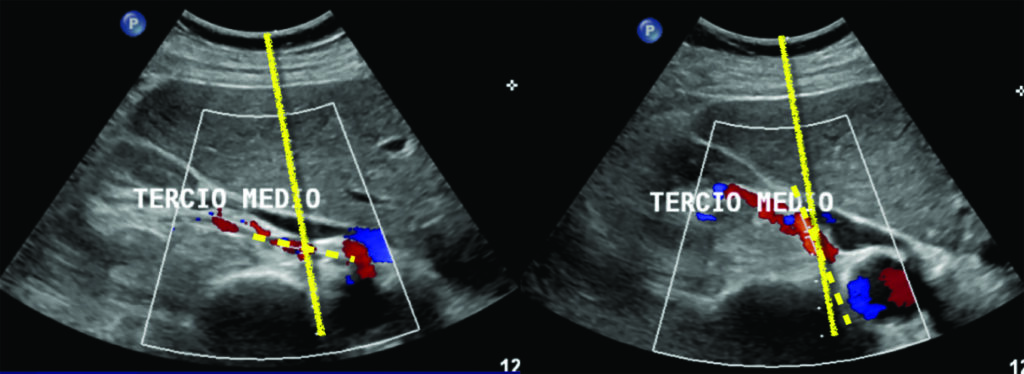

Determinación extrarenal. Esta determinación se realiza midiendo la velocidad del pico sistólico y la velocidad diastólica final de la arteria renal a nivel de ostium, en el tercio medio y el hilio renal. También en este caso se calculan el índice de resistencia y el tiempo de aceleración, y deben realizarse no menos de tres determinaciones para confirmar el diagnóstico.

La principal limitación del estudio extrarenal es el meteorismo, aunque también lo afectan la obesidad, los movimientos respiratorios, la tortuosidad arterial y un ángulo de incidencia incorrecto (correcto <60º) (Fig. 4) (14).

A. Velocidad del pico sistólico es la determinación de la velocidad máxima del flujo sanguíneo durante la sístole. Utilizando como criterios de estenosis los descriptos en la Tabla 1. Compartimos dos casos (Fig. 5, Fig. 6), con mediciones normales y patológicas.

Habitualmente se puede obtener un espectro de onda para el análisis de la velocidad del pico sistólico en el 92% de los casos. En el 8% restante, la arteria renal se visualiza parcialmente.

Consideramos que el eco Doppler color es útil para determinar el grado de evolución de la enfermedad renovascular, es decir, si la estenosis es moderada o severa, con el objetivo de instituir las medidas terapéuticas necesarias para preservar la función renal. La historia natural de estos pacientes muestra que la estenosis de la arteria renal tiende a progresar en el 20 a 40% de los casos y frecuentemente lleva a la oclusión del vaso comprometido. La presencia de flujo turbulento a nivel de la estenosis aumenta la agregación plaquetaria favoreciendo la trombosis y por ende la progresión de la lesión estenótica.